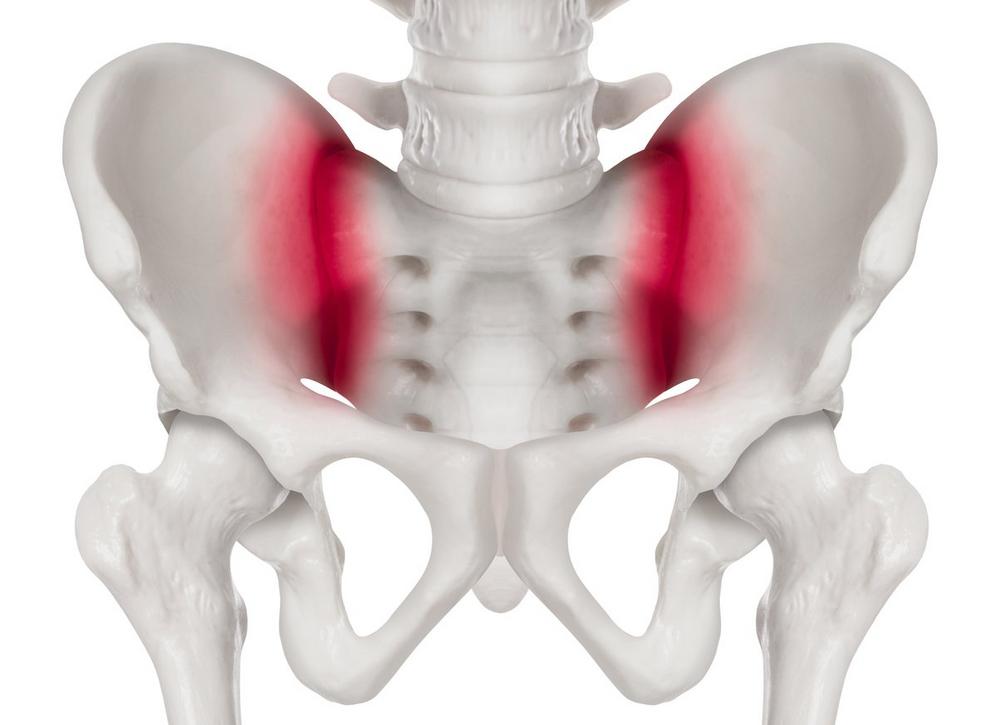

Wie so oft rücken manche Bereiche des Körpers erst dann in den Blickpunkt, wenn sie sich schmerzhaft zu Wort melden. So auch das Iliosakralgelenk, kurz ISG genannt. Es befindet sich im untersten Bereich der Wirbelsäule. Genauer gesagt zwischen dem Ilium und dem Sakrum. Beim Ilium handelt es sich um den flügelartigen Teil des Beckenknochens, beim Sakrum um einen dreieckigen Knochen, der aus fünf miteinander verschmolzenen Wirbeln besteht.

„Das Iliosakralgelenk hat vor allem drei wichtige Aufgaben, sagt Dr. Reinhard Schneiderhan vom gleichnamigen medizinischen Versorgungszentrum in München-Taufkirchen. „Allen voran die Kraftübertragung zwischen dem Rumpf und den unteren Extremitäten, beim Gehen, Laufen und Heben schwerer Lasten. Es trägt aber auch zur Dämpfung von Stößen bei und ist wichtig für eine aufrechte Haltung.“ Mit anderen Worten: Es muss großen Belastungen standhalten können. Nötig dafür sind ausreichend starke Muskeln und Bänder. Doch genau diese sind bei vielen Menschen oft nicht stark genug. Stichwort: Bewegungsmangel.

Meist treten die Probleme beim falschen Heben schwerer Gegenstände auf, oder wenn man ins Leere tritt. Rückenerkrankungen wie Spondylolisthesis, Entzündungen oder degenerative Wirbelsäulenveränderungen könne ebenfalls die Ursache sein. „Relativ häufig ist das ISG-Syndrom bei Läuferinnen und Läufern, die auf Krafttraining verzichten“, sagt Dr. Schneiderhan. „Bei ihnen liegt häufig ein Ungleichgewicht zwischen hüftbeugender und hüftstreckender Muskulatur vor.